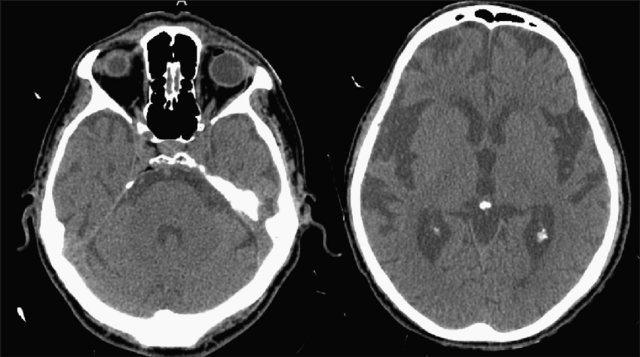

• Neuroimagen

Neuroimagen

Más recientemente, el desarrollo de las neuroimágenes han permitido un desarrollo más práctico del estudio de la neurología con una identificación más sencilla y menos invasiva de las estructuras, de las patologías y de las condiciones de las personas. Han permitido desarrollar patrones anatómicas para enfermedades que antes se creían desconocidas o pobremente asociadas a la neuroanatomía como las condiciones psiquiátricas, entre otros